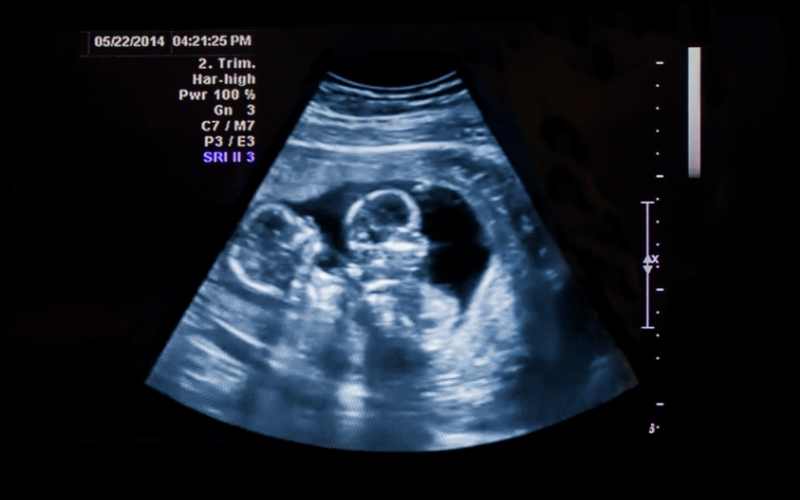

Thông thường, khi ở tuần thứ 17, thai nhi sẽ nặng khoảng 140 gam và chiều dài từ đầu tới mông khoảng 13cm. Dựa theo chỉ số tiêu chuẩn đó, mẹ có thể theo dõi sự phát triển của con và điều chỉnh chế độ dinh dưỡng cho phù hợp.

Trong giai đoạn thai kỳ được 17 tuần, nhịp tim của bé đập nhanh hơn so với người lớn, dao động ở mức 150 nhịp/phút nên mẹ không cần quá lo lắng. Các cử chỉ, hoạt động của bé cũng diễn ra với tần suất nhiều hơn và mạnh hơn. Vì vậy, mẹ có thể dễ dàng nhận ra mỗi lần bé đạp, duỗi tay, duỗi chân hay vặn mình.

Bên cạnh đó, một số cơ quan, bộ phận quan trọng khác của cơ thể bé cũng bắt đầu hình thành và phát triển nhanh chóng. Khi đi siêu âm, mẹ sẽ dễ dàng bắt trọn được khoảnh khắc đáng yêu và thay đổi về hình thể của bé. Cụ thể:

Cơ quan sinh dục của bé phát triển: Nếu là bé trai, mẹ có thể nhìn rõ tinh hoàn khi đi siêu âm. Còn nếu là bé gái thì ống dẫn trứng và tử cung được hình thành nhưng mẹ sẽ khó có thể quan sát thấy.